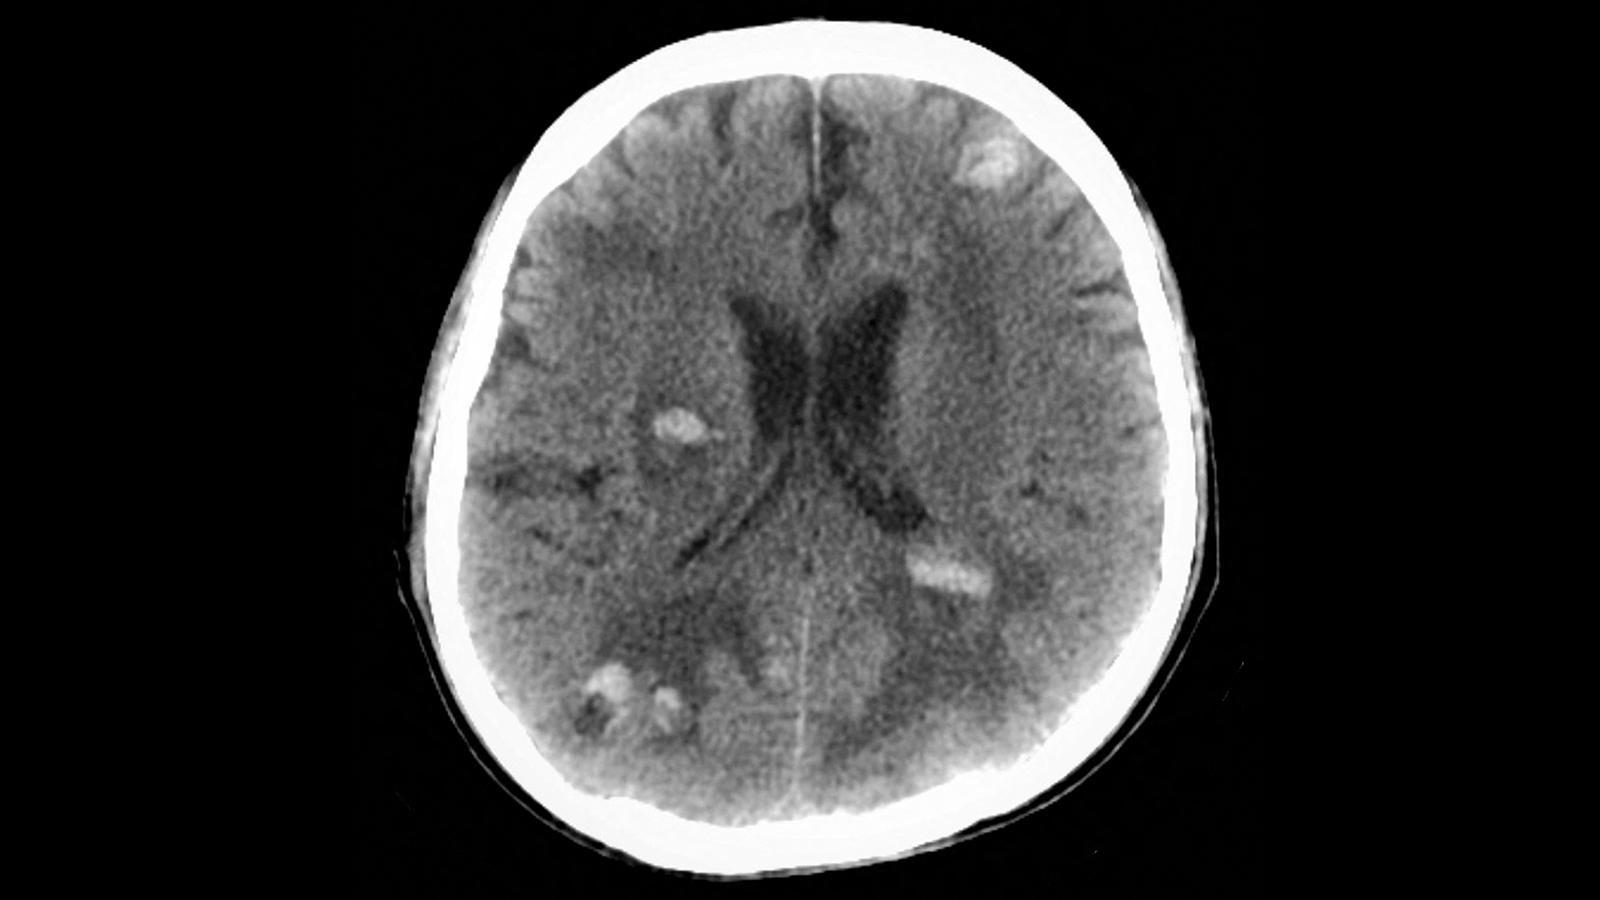

(MedPage Today) — GLP-1 receptor agonist use was associated with a lower risk of death in cancer patients with brain metastases and type 2 diabetes, a retrospective cohort study found.

Within 3 years of a first recorded brain metastasis, patients…